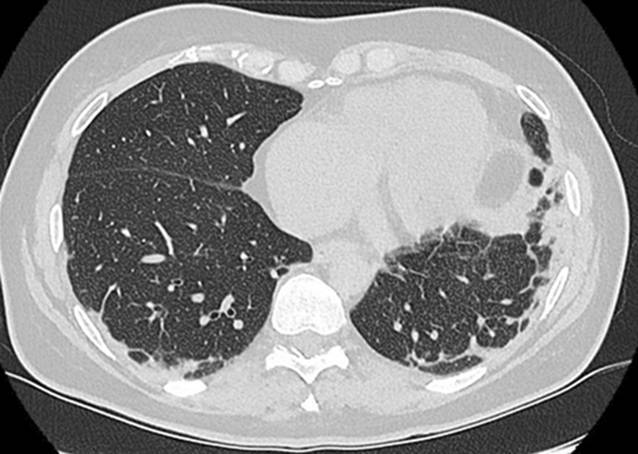

Laborchemisch bestanden keine relevant erhöhten Entzündungszeichen und normale Werte der Kreatinkinasen (CK). Es erfolgte eine umfangreiche Diagnostik ohne Hinweis auf eine infektiöse oder maligne Genese der Symptomatik. Initial zeigten sich in der Computertomographie (CT) des Thorax beginnende subpleural, peribronchial und basal betonte Konsolidierungen (Abb. 4). Lungenfunktionell zeigten sich eine restriktive Ventilationsstörung und eine Diffusionsstörung (Tab. 1). In der erweiterten Labordiagnostik ergaben sich der Nachweis von antinukleären Antikörpern (ANA) mit einem Titer von 1:100, positive Anti-Ro-52-Antikörper sowie gegen das Melanom-Differenzierungsantigen 5 gerichtete Antikörper (Anti-MDA5-Antikörper). Hinweise auf ein Sjögren-Syndrom wie eine Sicca-Symptomatik oder ein positiver Schirmer-Test bestanden zu diesem Zeitpunkt nicht. Wir stellten die Diagnose einer amyopathischen MDA5-positiven Dermatomyositis.

Es erfolgte eine Therapie mit Prednisolon (1 mg/kgKG) und Azathioprin (150 mg/Tag) über 4 Monate. Unter der Predisolon-Reduktion bis 20 mg/Tag zeigten sich rezidivierende Gottron-Papeln, ein erneutes heliotropes Exanthem sowie eine beginnende Muskelschwäche der proximalen Extremitäten. Bei klinisch deutlich progredienter Belastungsdyspnoe und auskultatorischem Knisterrasseln zeigten sich im CT-Thorax ebenfalls progrediente Konsolidierungen, sodass eine Therapie mit Cyclophosphamid (dreimalige Gabe von 1000 mg) erfolgte (Abb. 5). Die geplante Gabe von 6 Infusionen à 1000 mg Cyclophosphamid wurde aufgrund der rasch progredienten Verschlechterung der respiratorischen und kutanen Manifestationen somit zugunsten eines Wechsels der Therapiestrategie unterbrochen. Bei einem Therapieversagen von Cyclophosphamid und weiter progredienter Lungenbeteiligung in der CT nach 4 Monaten erfolgte eine zweimalige Gabe von 1000 mg Rituximab (im Abstand von 2 Wochen). Nach einem weiteren Intervall von 4 Monaten war keine Prednisolon-Reduktion unter eine Tagesdosis von 30 mg möglich. Es erfolgte bei weiter progredienter Belastungsdyspnoe eine Umstellung der Basistherapie auf Mycophenolat-Mofetil (MMF), 2 g/Tag.